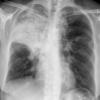

Case 2 Lingular pneum PA

Date: 04/17/2005

Views: 5955